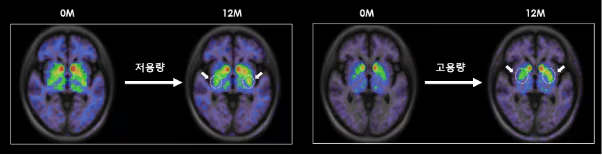

根據S.Biomedics公司本月初在奧地利維也納舉行的國際會議上公布的研究結果,低劑量和高劑量治療組患者的運動功能評分較植入前均提高了高達28.9%。低劑量和高劑量組患者的精神和情緒癥狀以及自主神經癥狀也均得到顯著改善。

低劑量和高劑量TED-A9植入一年后的腦成像。

尤其是在干細胞治療帕金森病植入一年后,對腦成像圖像進行分析后發現,多巴胺轉運蛋白的表達較植入前有所增加。干細胞治療的開發者、延世大學醫學院金東旭教授指出:“這表明干細胞在腦內存活,成熟為多巴胺神經細胞,并與周圍區域和突觸(神經細胞之間的連接)形成整合。”他補充道:“這可以被視為帕金森病中替換死亡多巴胺神經細胞的根本治療機制的有力證據?!?/p>